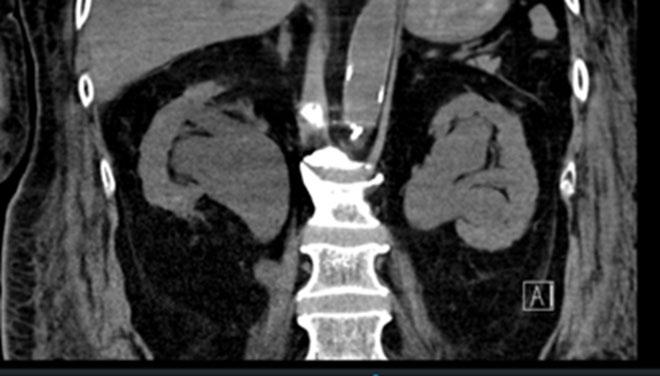

necrotizing granulomatous infection with negative cultures. However, urine culture was significant for pyuria and acid-fast bacilli. Cystoscopy was notable for bilateral hydronephrosis associated with significant bladder inflammation and ureteral strictures. He was treated with levofloxacin 750 mg daily for 6 months, rifampin 600 mg daily for 6 months, pyrazinamide 1,500 mg daily for 2 months, ethambutol 1,200 mg daily for 2 months, and pyridoxine 50 mg daily for 6 months as it was resistant to isoniazid (Figure 1).

Figure 1: CT of abdomen shows severe hydronephrosis in the right ureter.